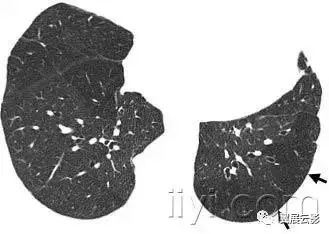

十八、小叶中心性:

解剖:小叶中心性用于描述次级肺小叶的支气管血管束中心区域。病理学上也用这一术语描述终末小支气管远端,位于呼吸性细支气管和肺泡管中心的病变。

CT:正常次级肺小叶中心的点状或者线状的密度增高影,胸膜下25px范围内最明显,代表小叶内的动脉,直径约1mm。

小叶中心性异常包括(1)结节(2)树芽征,提示小气道病变(3)由于临近间质的增厚或者浸润导致小叶中心结果更加清晰(4)小叶中心性肺气肿导致的异常低密度。

附图为小叶中心性肺气肿